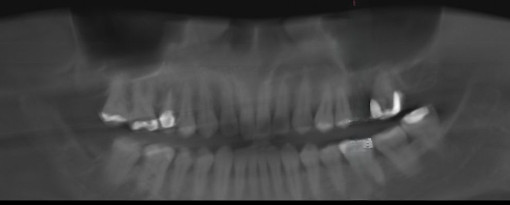

当院では、世界的歯科機器メーカー「デンツプライシロナ社」が開発した口腔内スキャナー『プライムスキャン(PrimeScan)』を導入しています。従来の印象材を使用しない“デジタル印象”により、精度・快適性・スピードすべてにおいて次世代のインプラント治療を提供しています。

CT×IOSでインプラントを入れる位置・深さ・角度まで立体的に設計し、ズレの少ない安全な治療計画が可能になります。